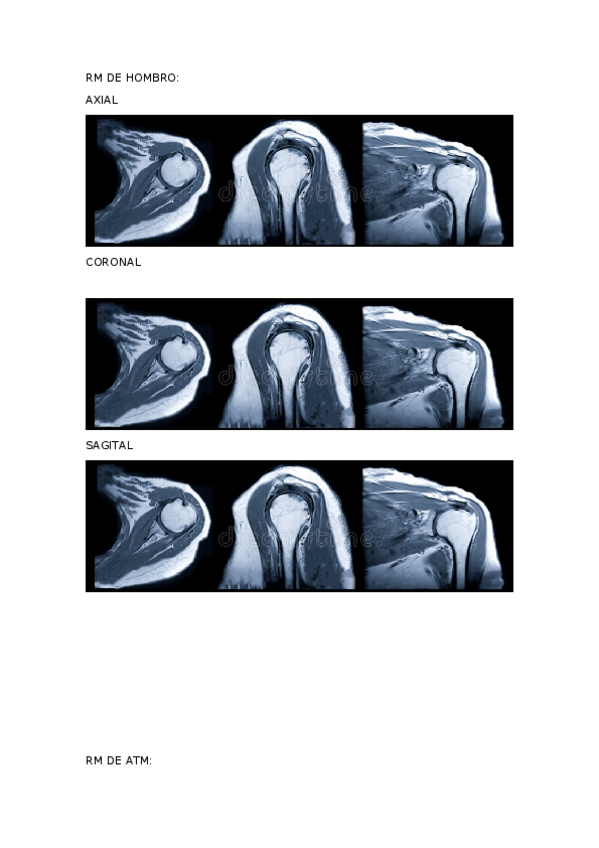

He publicado nuevos apuntes de Técnicas de Imagen por Resonancia Magnética: ACTIVIDADES-RM-1.docx

word